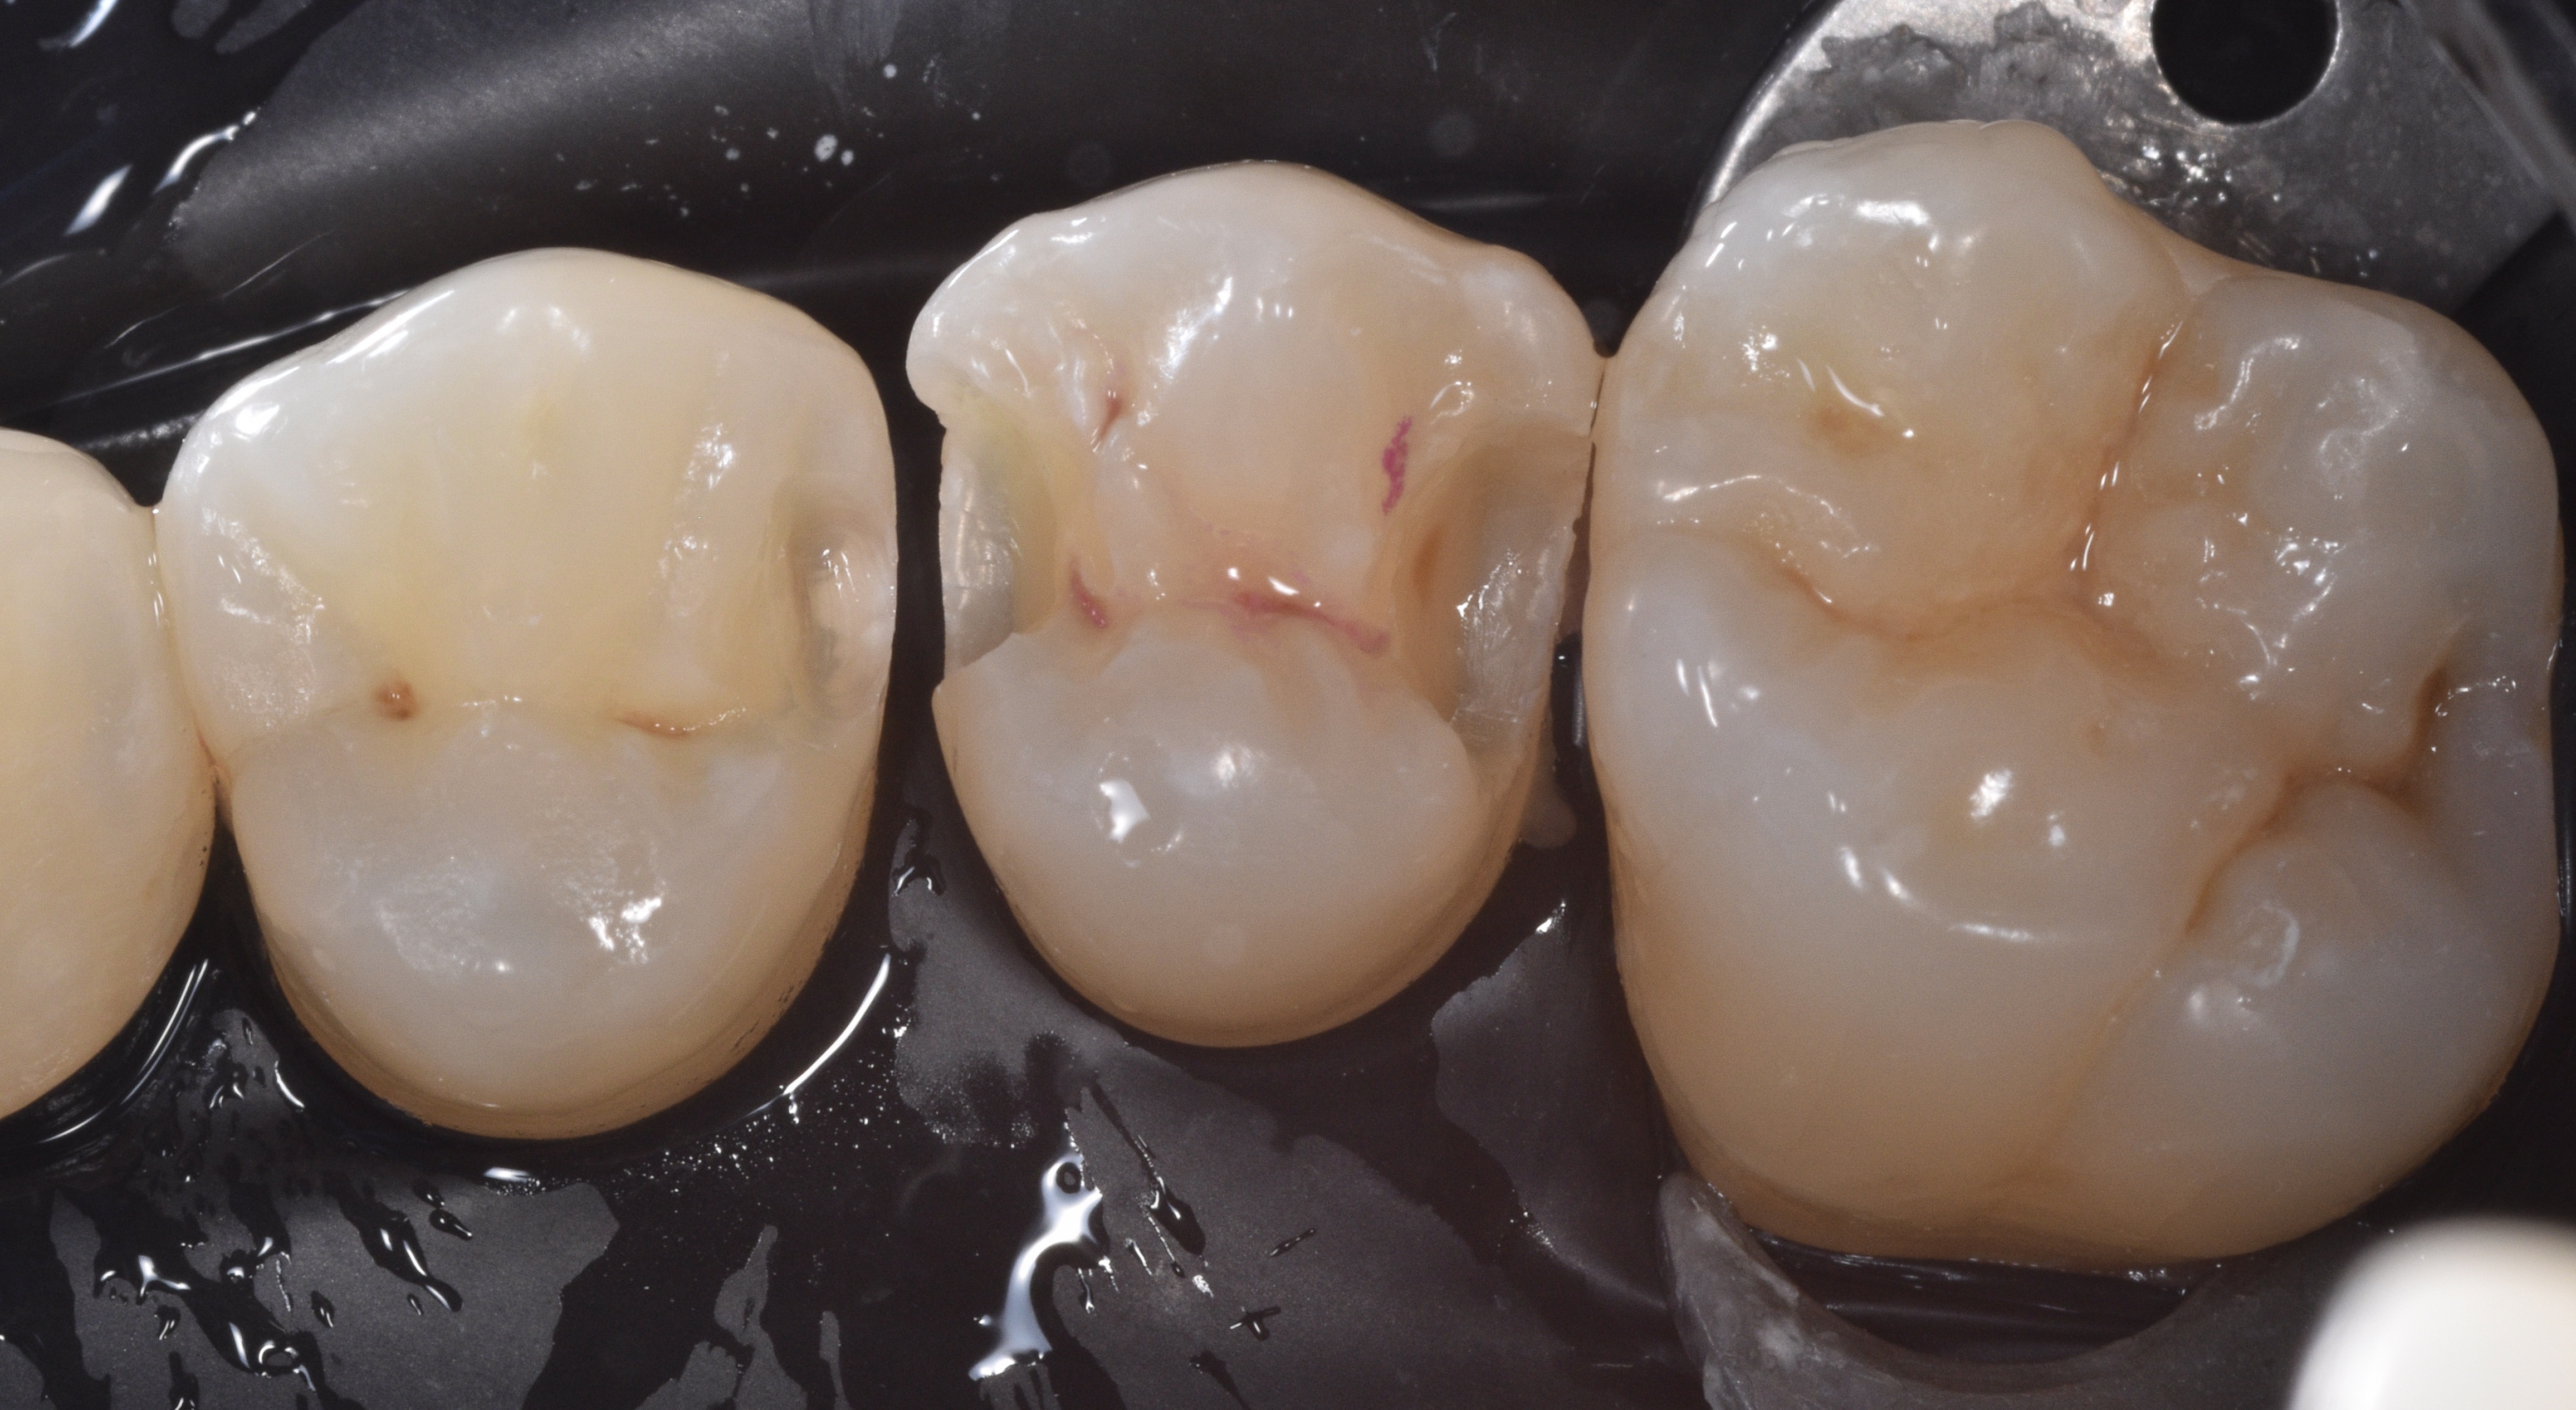

We remove the sectional matrix system and place it in between teeth #12-13 to restore both preparations simultaneously (Figure 7). See how the Quad wedge split tip contours the bands even prior to placing the ring.

Make sure that the black arrow is always placed towards the lingual and that it pushes each end of the split wedge towards the mesial and distal as seen on Figure 8